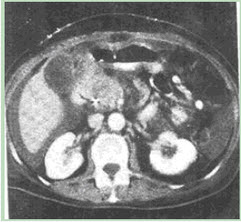

患者男性,49岁,反复腹痛,进行性黄疸月余,CT图像如下,最有可能的诊断是()。

C、胰头癌

C